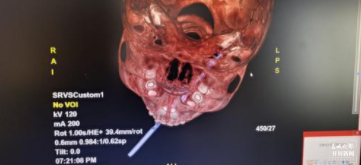

医生对孩子进行初步检查后发现,孩子神志清醒,各项生命体征平稳。为了查清楚木棍插入的深度和具体位置,医生对孩子的头部进行了CT扫描 ,结果显示,这根棍子自孩子左侧口腔内戳入,直插颈部,位于颈动脉三角内。(颈动脉三角:颈动脉位于颈部,因其内含有颈内静脉及其属支、颈总动脉及其分支而得名,除血管外还有舌下神经,副神经等神经从这里穿行)。

贸然拔出竹签,会导致孩子大失血,造成失血性休克,死亡风险极高。为了给手术医师更好地评估手术风险,CT室值班医师给患儿进行了三维重建,长约15cm左右的棍子插进体内约7cm,直达患儿颈后,从患儿颈背部可以用手触及竹签顶端。